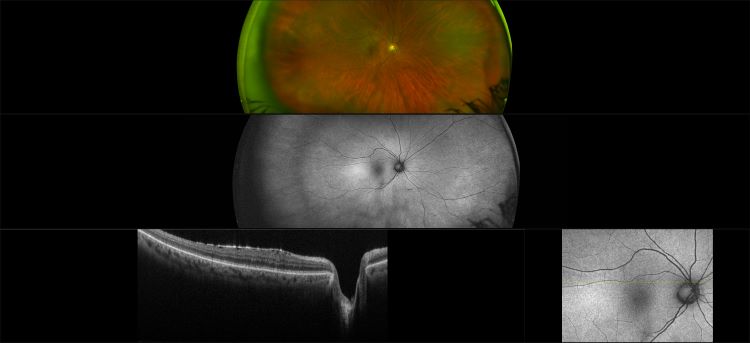

Monaco - Epiretinal Membrane RG, AF, OCT

An epiretinal membrane is a fibrocellular tissue found on the inner surface of the retina. It is semi-translucent and proliferates on the surface of the internal limiting membrane.

An epiretinal membrane is a fibrocellular tissue found on the inner surface of the retina. It is semi-translucent and proliferates on the surface of the internal limiting membrane.